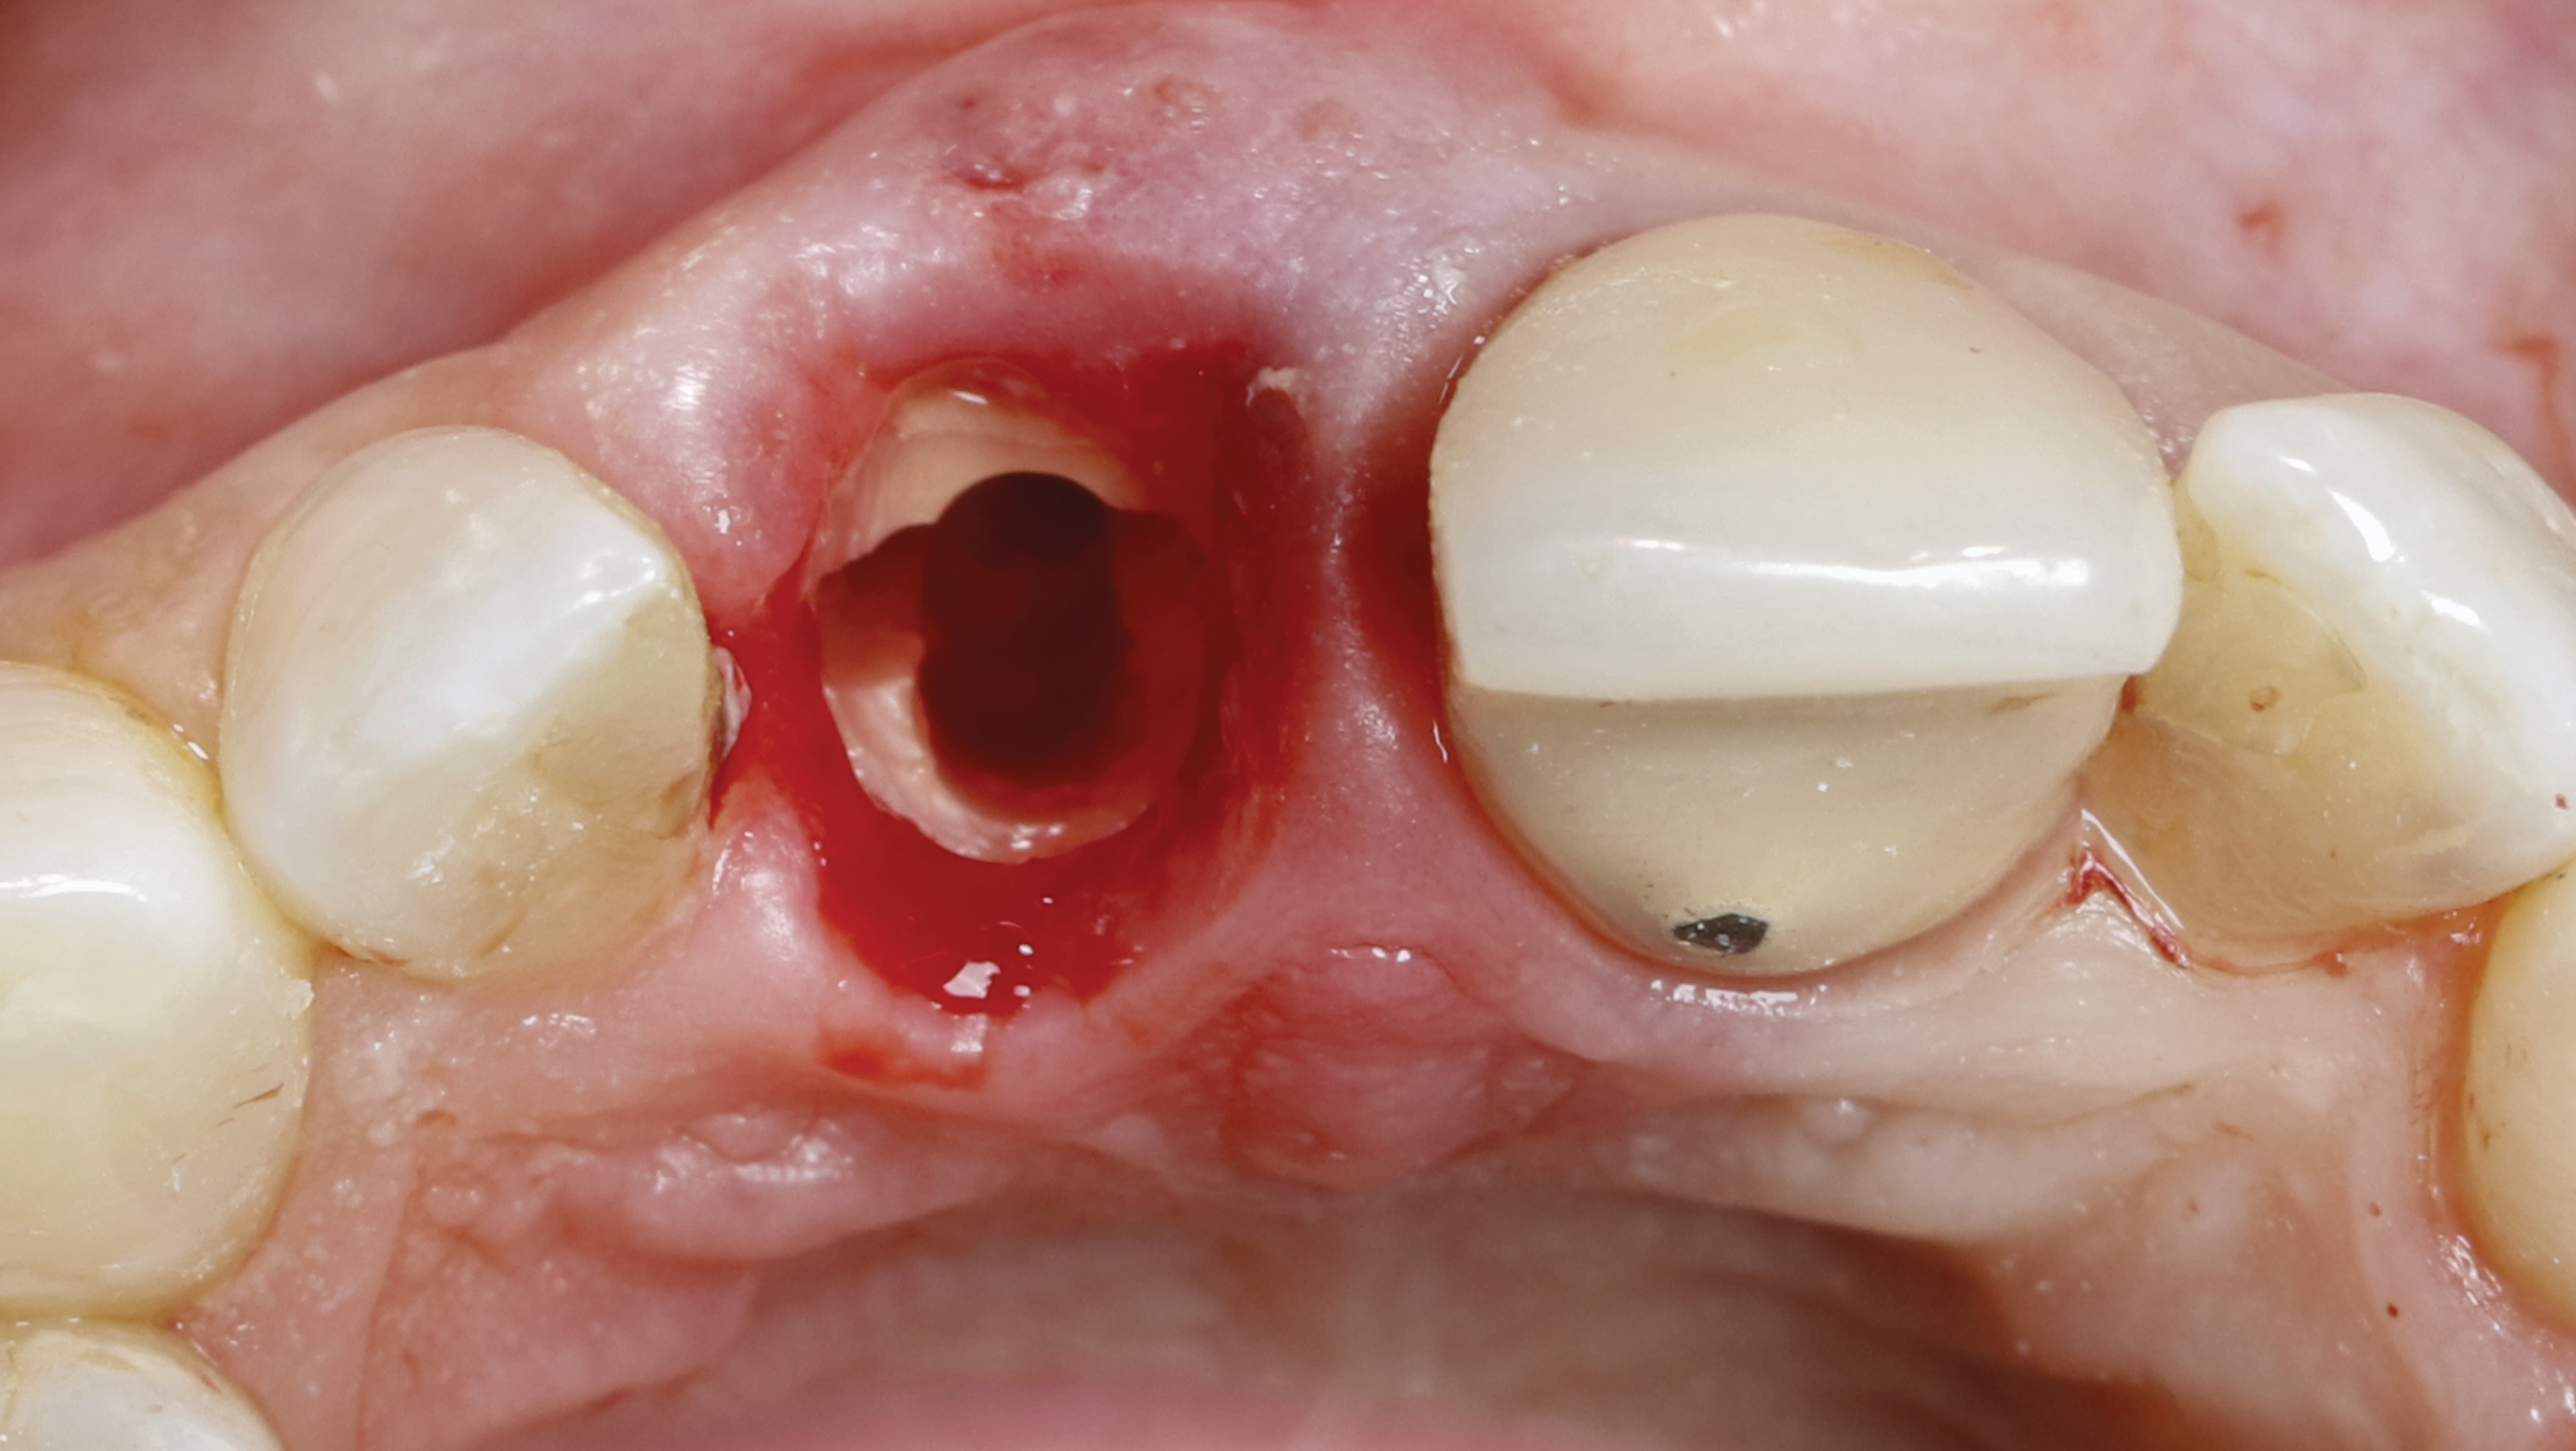

Step 2 - Establish the restorative zone: The restorative zone is established using a specified diamond wheel bur (Meisinger 909G-031) to flatten the root to bone level working from inside to outside, following a curve from the buccal to the interproximal bone, avoiding reduction in the interproximal bone height. The goal of this step is to separate and remove the outer occlusal ring of dentin (Figure 6).

Fig 6. SPOT Step 2: The restorative zone is established using a diamond wheel bur (Meisinger 909G-031) to flatten the root to bone level, working from inside to outside.

Figure 6